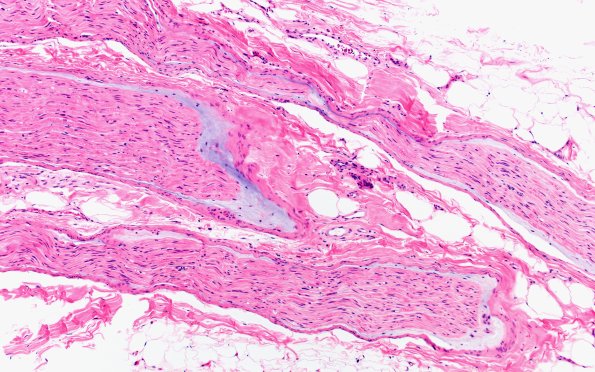

Washington University Experience | PERIPHERAL NEUROPATHY | 4 AXONAL DEGENERATION | 5 Edema | 4A1 Edema, subperineurial (Case 4) H&E 1

4A1,2 These small fascicles show axon loss and increased granular fluid in the sub-perineurium. (H&E)